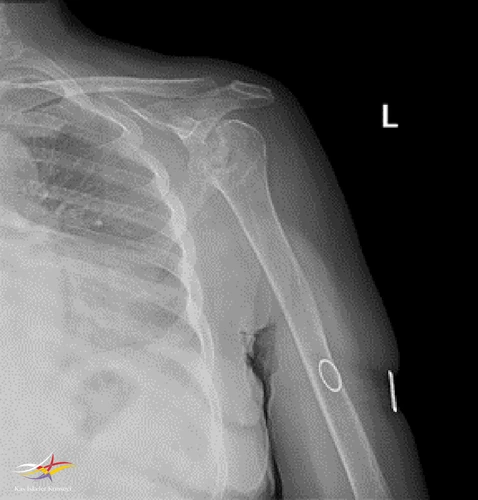

Resim 1. Sol omuz direkt grafi-1.

Sol Omuz MRG: Glenoidde kortikal düzensizlikler, lokalize defektif alanlar ve bu düzeyde subkondral milimetrik kistlerin eşlik ettiği medüller hafif hiperintens ödem izlenmektedir. Humerus baş kesiminde medialde de geniş bir alanda defektif görünüm mevcuttur. Buna komşu humerus başında milimetrik kistler ve medüller ödem izlenmektedir.

Humerus başında ve glenoid de osteofitik dejeneratif değişiklikler mevcuttur. Gleno-humeral eklem aralığı anterior inferiorda daralmıştır.Eklem aralığında sıvı miktarında belirgin artış izlenmedi.

Humerusta tüberkülüm majusta milimetrik kist - medüller ödem benzeri sinyal değişikliği dikkati çekmektedir.

Akromioklaviküler eklemde minimal dejeneratif hipertrofi izlenmekte olup eklem aralığı yaklaşık 5 mm ölçülmüştür ve normal sınırlar içerisindedir. Subakromial yağ mesafesi basılıdır. Akromion Tip 2 konfigürasyondadır. Glenoid labrumlar değerlendirilemedi. Biceps uzun başı tendonu normaldir. Supraspinatus tendonunda tendinozis izlenmektedir.